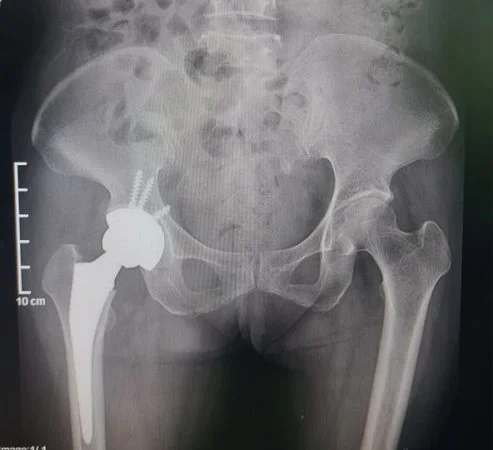

Hoại tử chỏm xương đùi là nguyên nhân gây đau mạn tính và hạn chế vận động khớp háng. Người bệnh nằm trong những đối tượng có yếu tố nguy cơ cao lại kèm theo các biểu hiện của bệnh hoại tử chỏm xương đùi, cần đi khám và được chẩn đoán bệnh sớm, không nên chủ quan để bệnh quá muộn. Phát hiện điều trị sớm giảm được tỷ lệ thay khớp háng cho người bệnh.

Nếu phát hiện những dấu hiệu của hoại tử chỏm xương đùi, bệnh nhân nên đến khám và điều trị sớm để dự phòng biến chứng. Hiện nay Khoa Ngoại Chấn thương Chỉnh hình – BV Thống Nhất đã triển khai phẫu thuật điều trị thay khớp háng cho các bệnh nhân bị hoại tử chỏm. Mọi chi tiết xin liên hệ